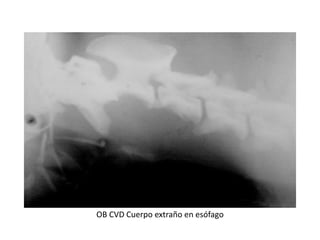

OB CVD Cuerpo extraño en esófago